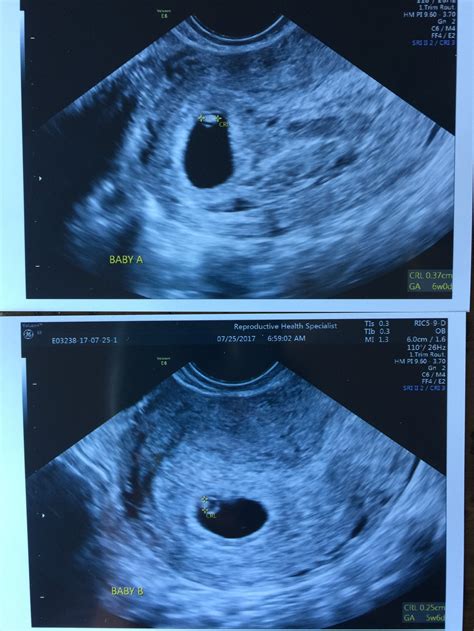

• Identification of Multiple Gestations: The ultrasound can detect the presence of twins or multiples, allowing for early preparation and specialized care.

• Gestational Sac: The presence of a gestational sac confirms the pregnancy. It appears as a small, fluid-filled structure within the uterus.

• Yolk Sac: By week 6, a yolk sac may be visible. This structure provides early nutrition to the embryo and is a positive sign of a healthy pregnancy.

• Fetal Pole: The fetal pole is the earliest visible structure of the embryo. It appears as a small, curved line within the gestational sac.

• Fetal Heartbeat: A fetal heartbeat may be detectable by week 6, although it is more commonly seen by week 7. The heartbeat appears as a flickering motion on the ultrasound screen.